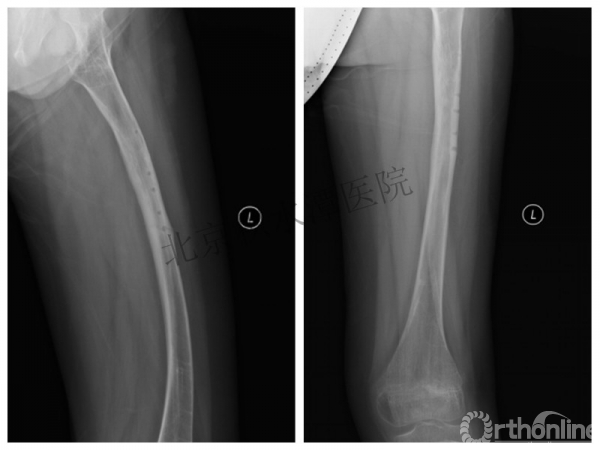

取板后再骨折→TEN

TEN取出后2个月